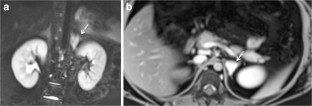

Fig. 1

Fig. 2

Fig. 3

Fig. 4

Fig. 5

Fig. 6

Fig. 7

Fig. 8

Fig. 9